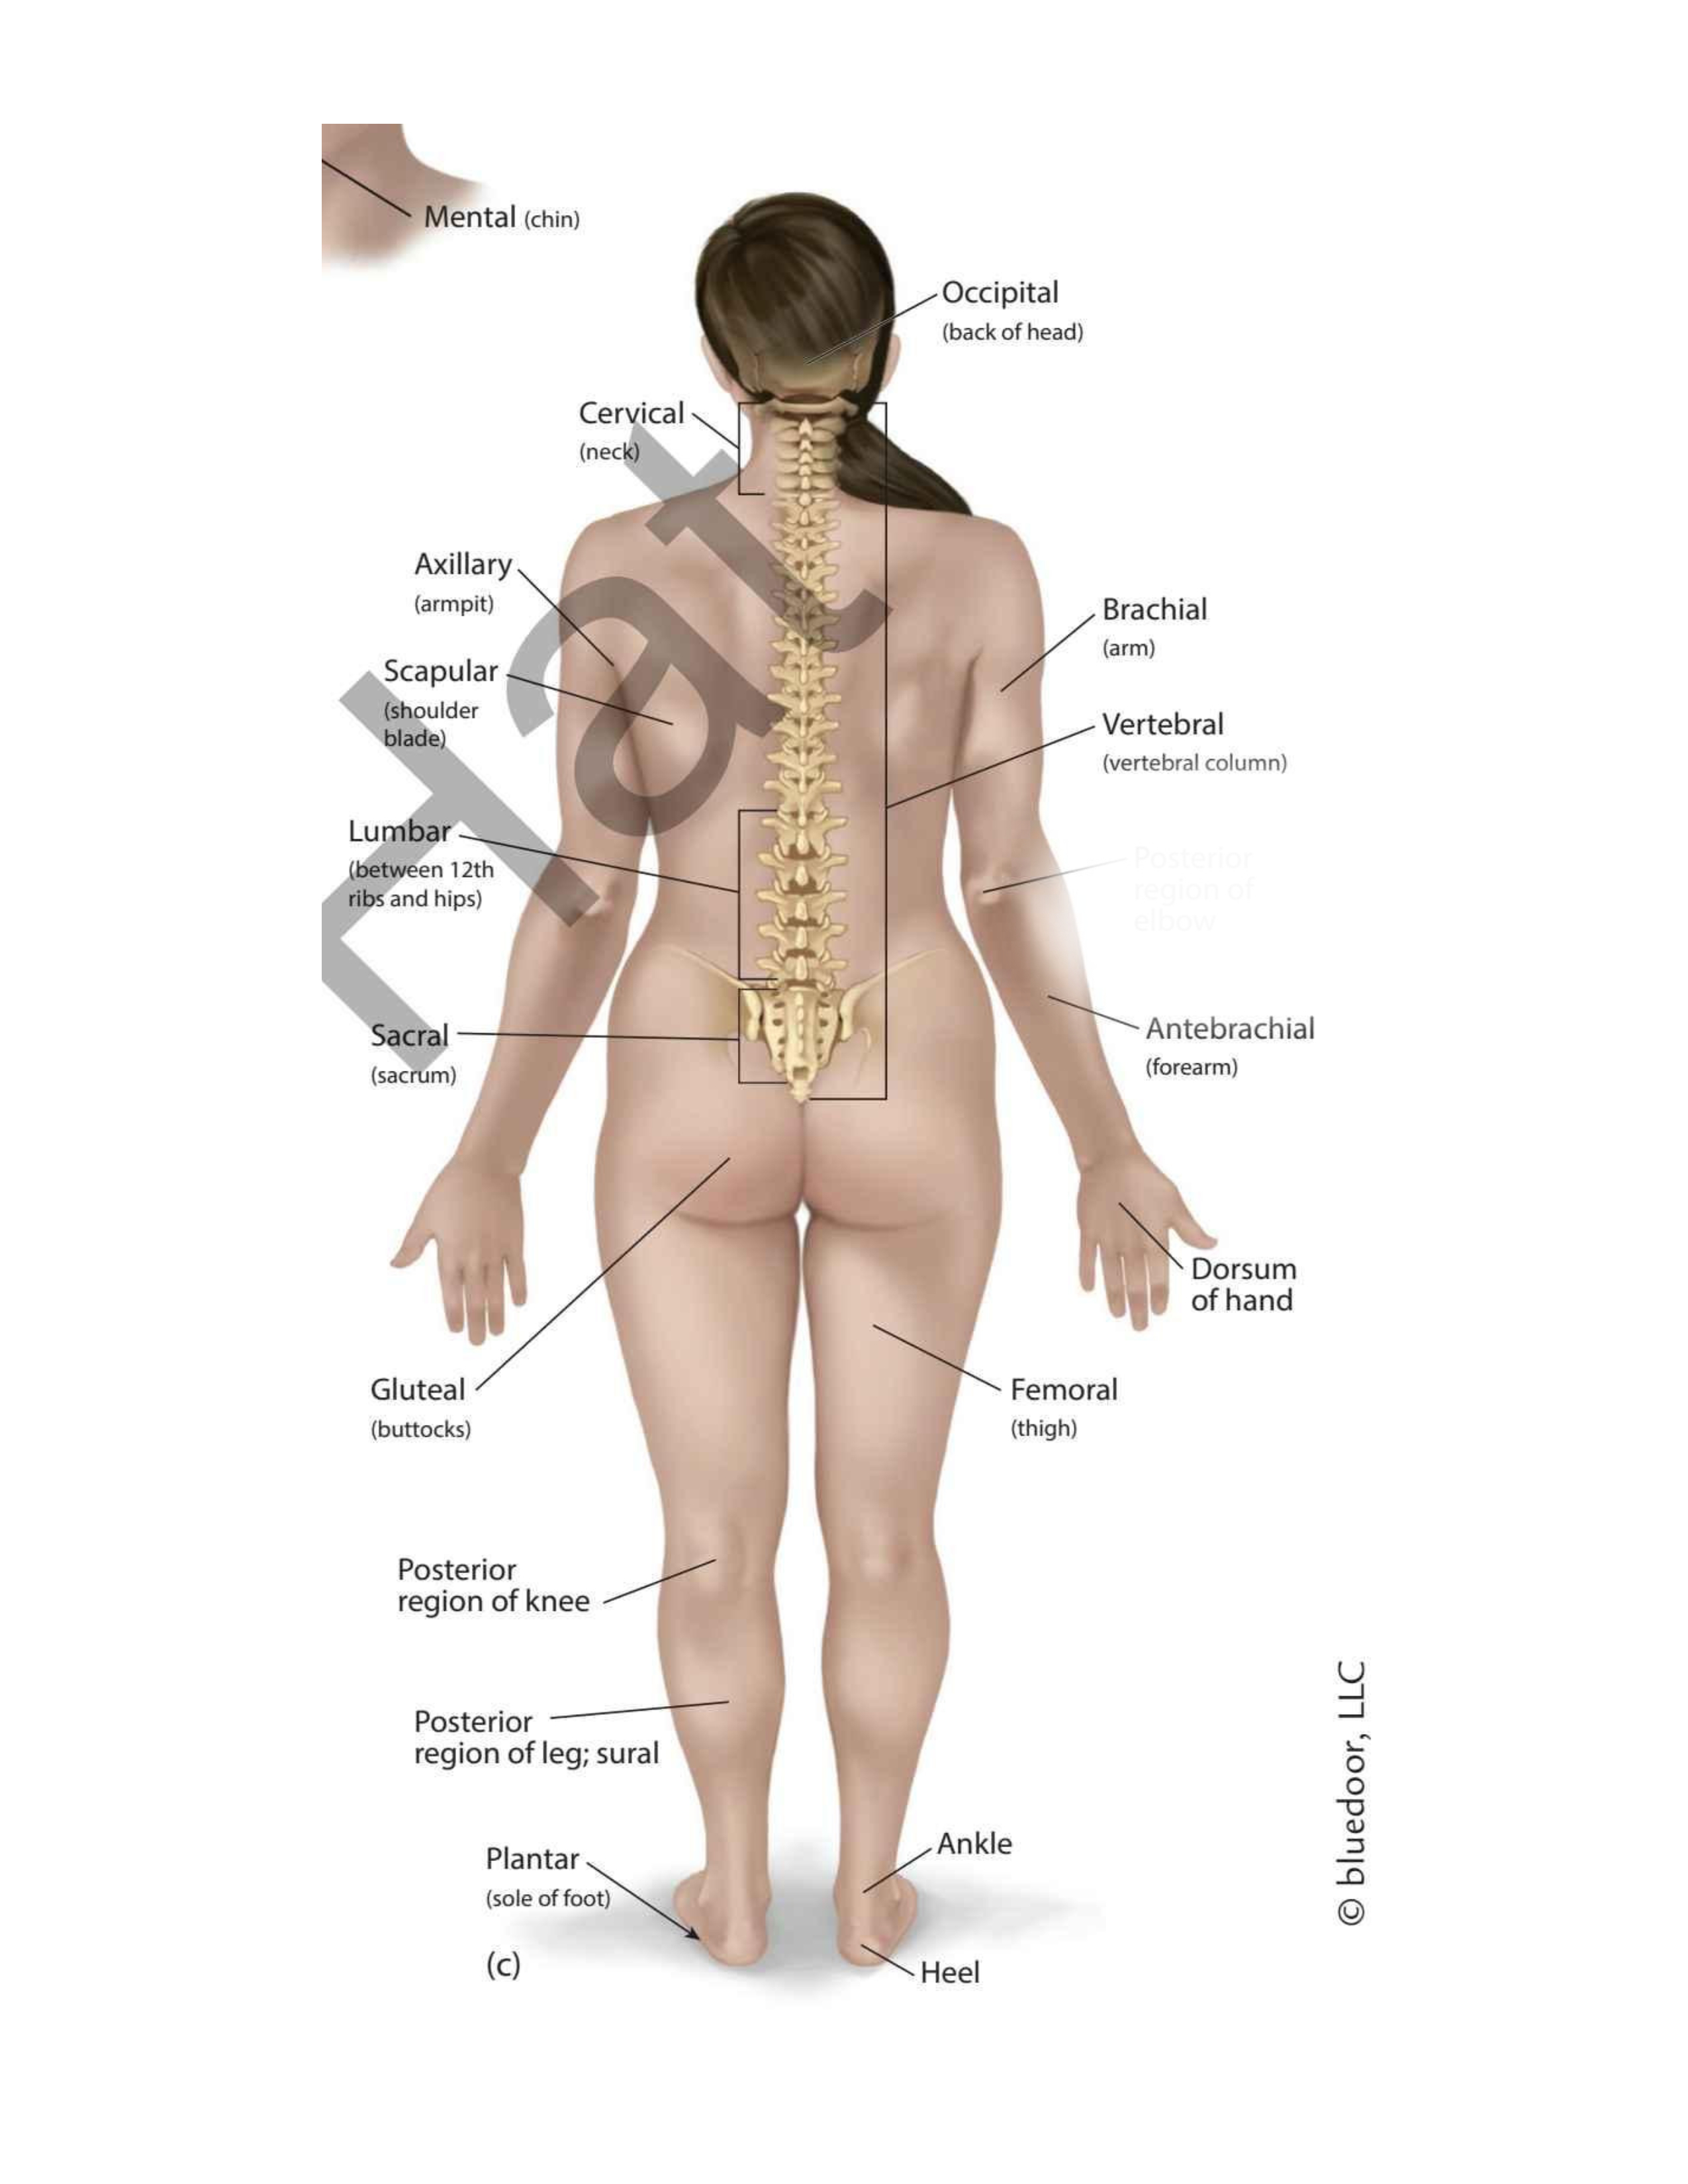

(forehead)

Frontal

(chin)

Mental

(wrist)

Carpal

(thigh)

Femoral

(elbow)

Antecubital

(back elbow)

Olecranal

(back knee)

Popliteal

(heel)

Calcaneal

(shoulder blades)

Scapular

(sole)

Plantar